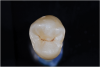

Fig 6. ICDAS code 0: Clinical appearance of stained fissure with no evidence of shadow or decalcification after drying.

Figure 6

Fig 7. ICDAS code 0: Sectioned tooth confirms stain not indicative of carious penetration of fissure.

Figure 7